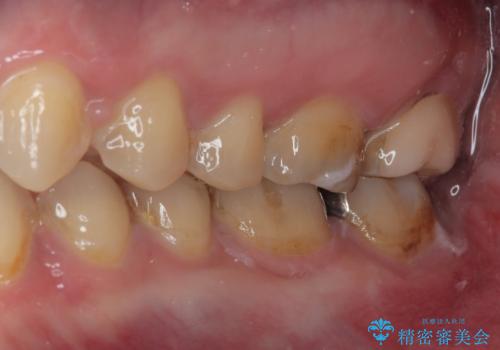

銀歯を白くしたい セラミックインレー修復

- 当院に矯正治療で通院されており矯正治療後に銀歯が目立つので白くしたいとのことでした。

拡大鏡視野下でメタルインレー、虫歯の除去を行い、セラミックインレーに適した形に整えました。